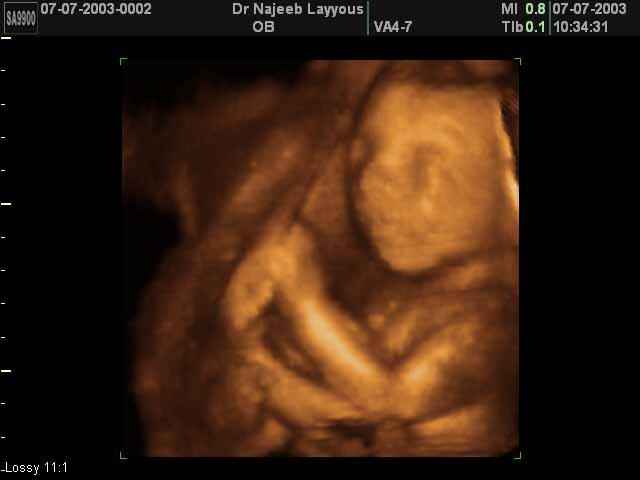

صور جانبية لرأس الجنين بجهاز الالتراساوند ثلاثي الأبعاد | الدكتور نجيب ليوس